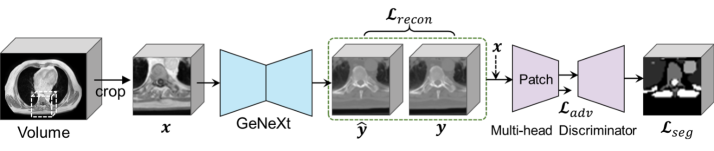

Refer to caption

Figure 1: Overview of GANeXt

As illustrated in Figure 1, the input volume is first cropped to a 3D patch, which is then fed into a GeNeXt generator to generate a synthetic CT patch. Next, a conditional PatchGAN discriminator [6] is used to distinguish the synthetic CT and the real CT patches. The whole model is implemented with PyTorch and the MONAI framework [2]. We describe the detailed structures of the generator and discriminator below.